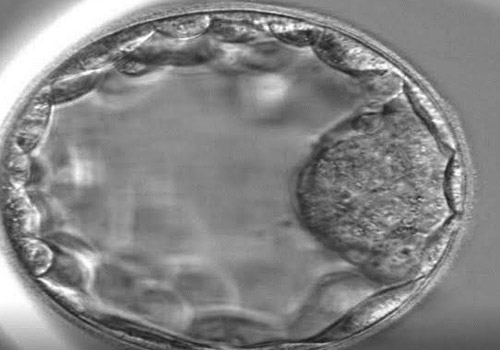

Blastocyst culture and transfer

Blastocyst culture involves keeping the embryos in special conditions in the laboratory until day 5 or 6 of development after follicular puncture.